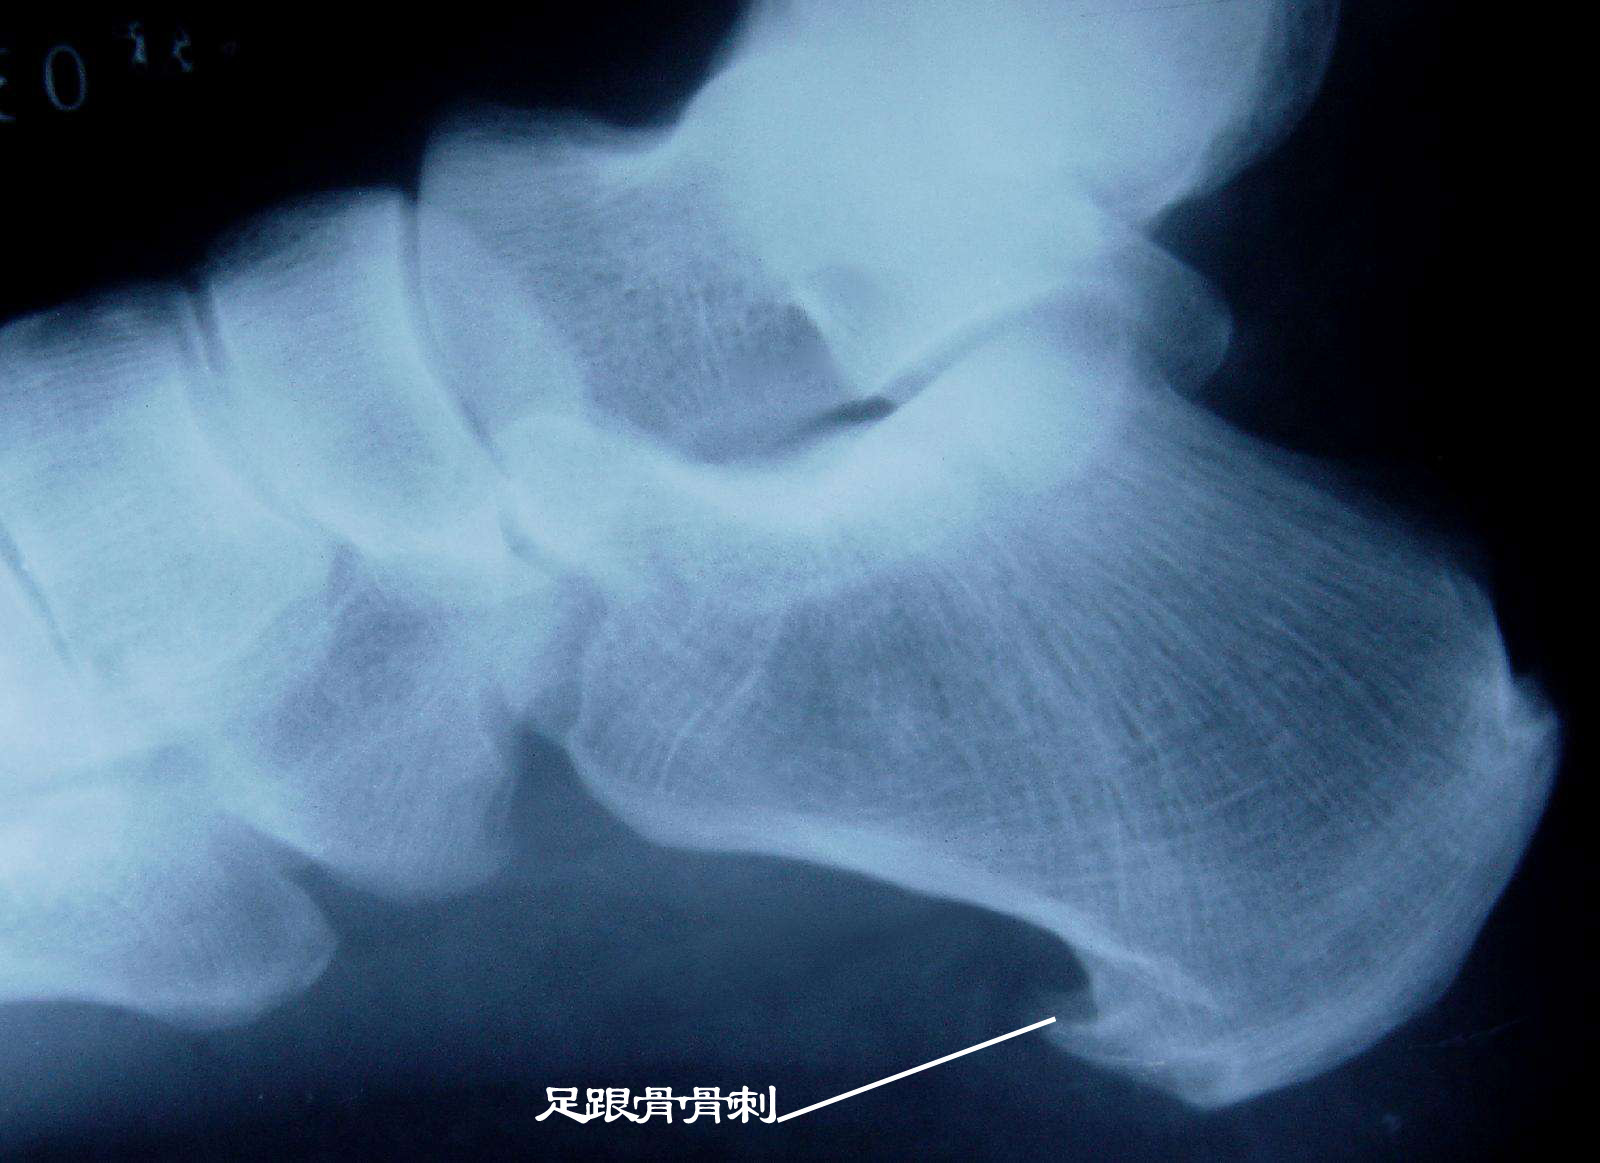

术前x线片显示跟骨增生骨刺明显.

脚跟骨骨刺

跟骨骨刺